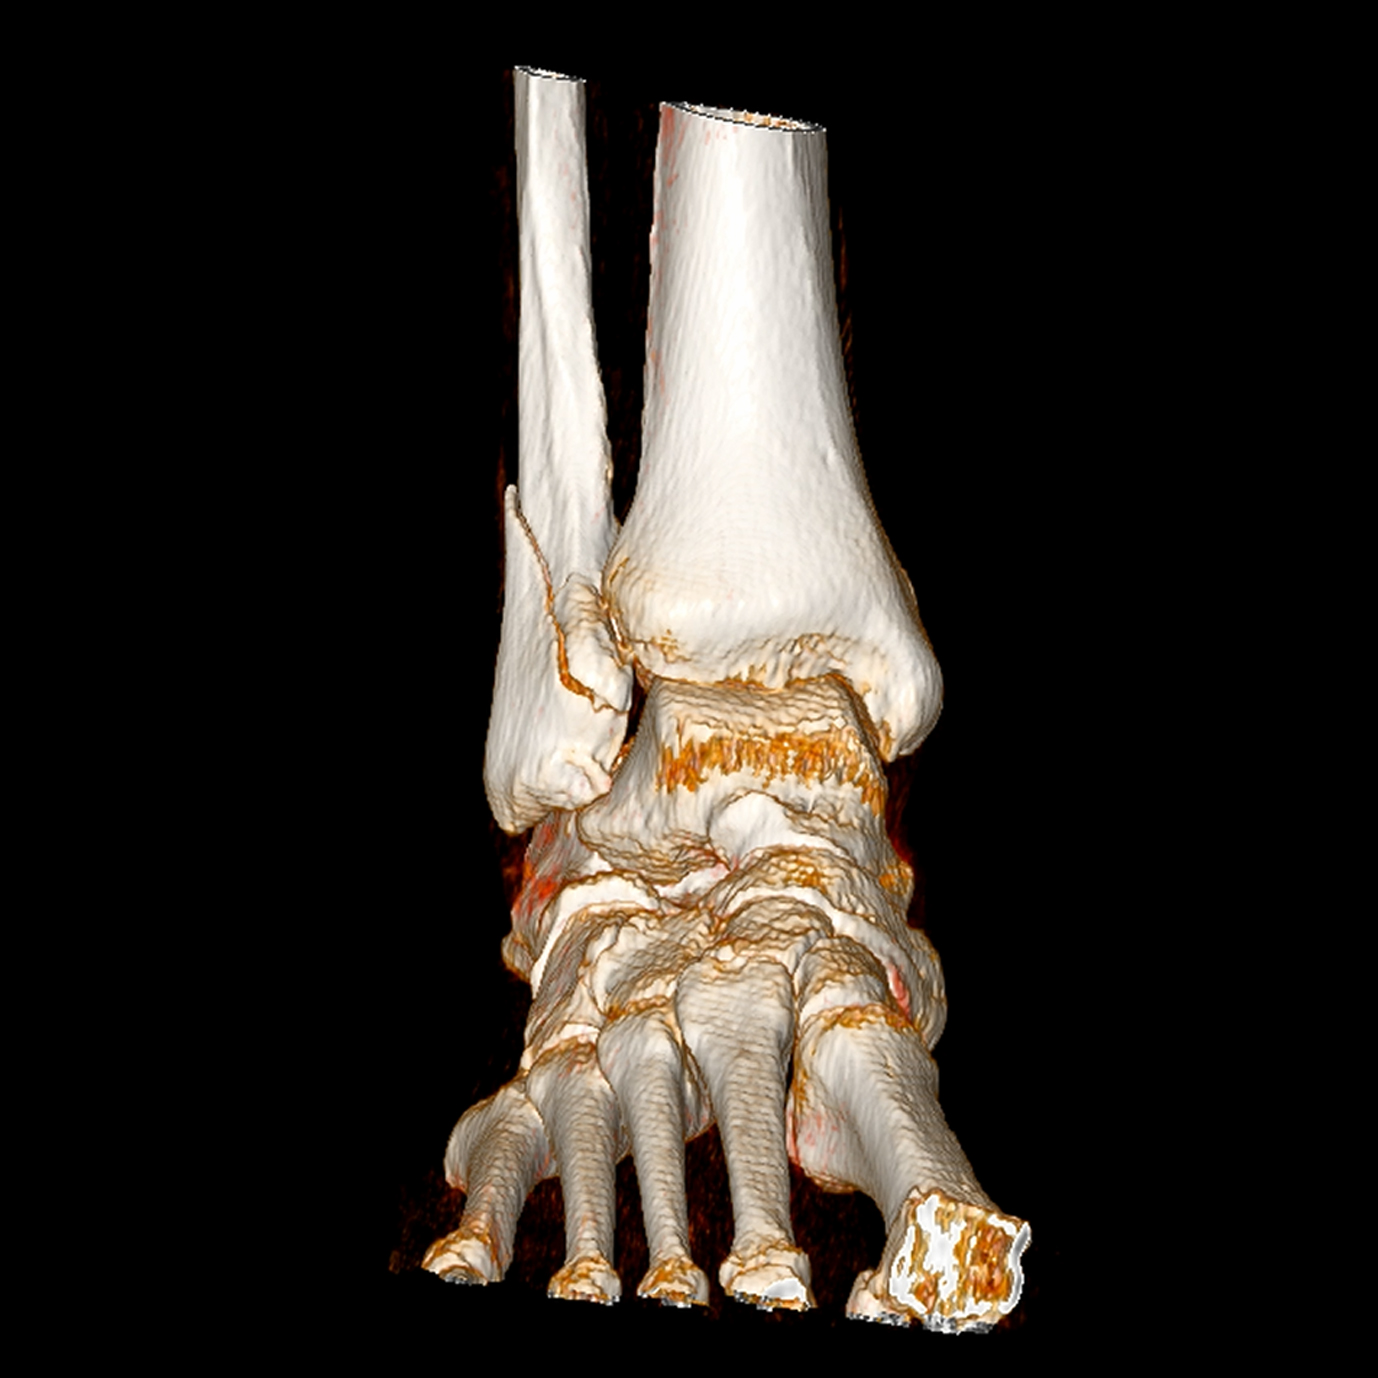

Ejemplos de estudios realizados en nuestra clínica.

con precisión avanzada para un diagnóstico confiable